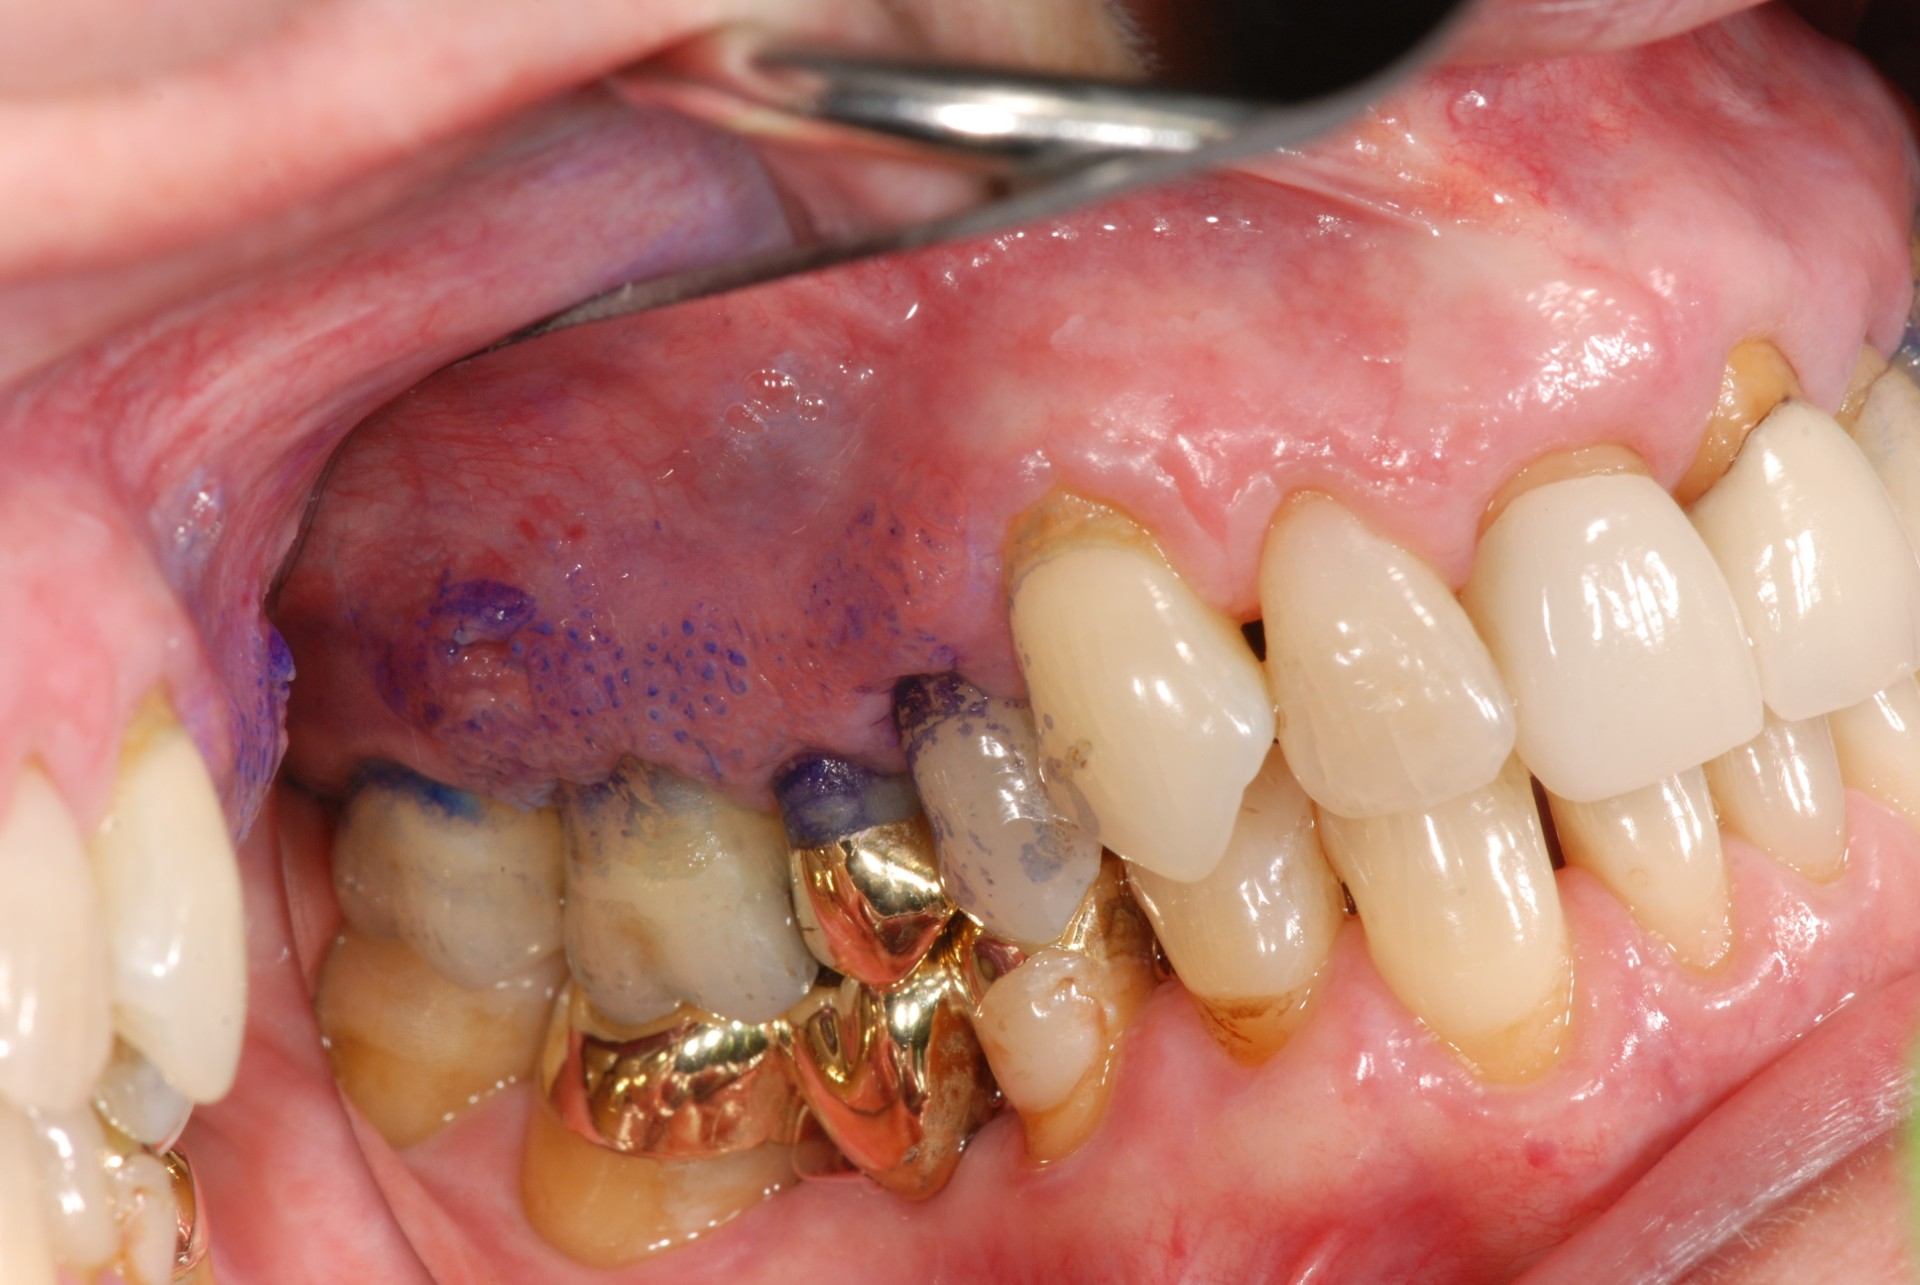

Figure 8. Irregular keratotic and erythematous lesion of the posterior maxillary gingiva with toluidine blue uptake. Histopathologic diagnosis: moderate to severe epithelial dysplasia.